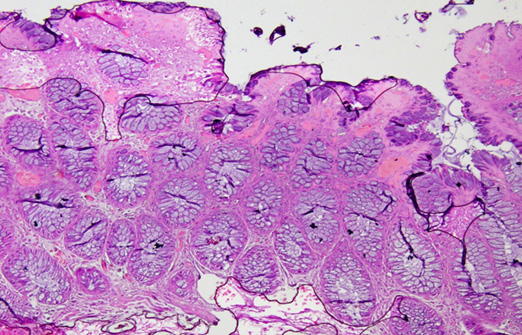

Photomicrograph

Figure 12: Photomicrograph of Adenomatous polyp Ki-67 expression: Positive (Case No: 48, IHC X 40x).